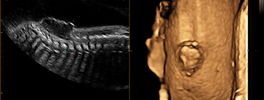

2D Sonography-Foetal Spine

Spinal Defect Sonography